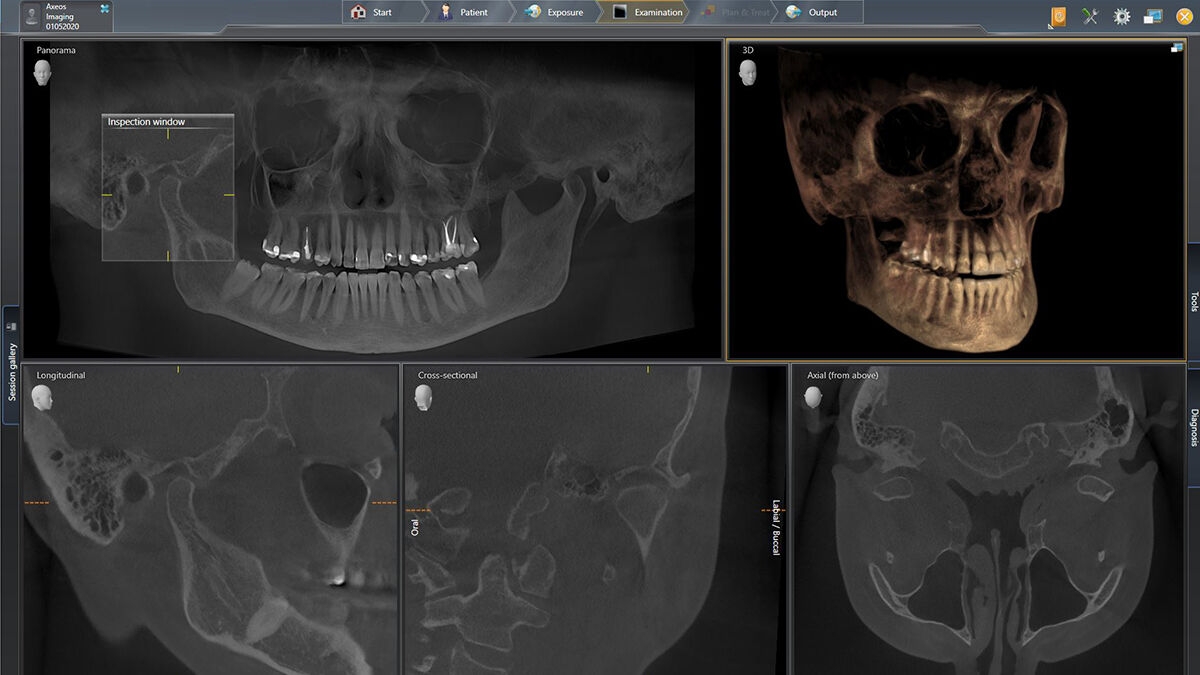

3D示例图